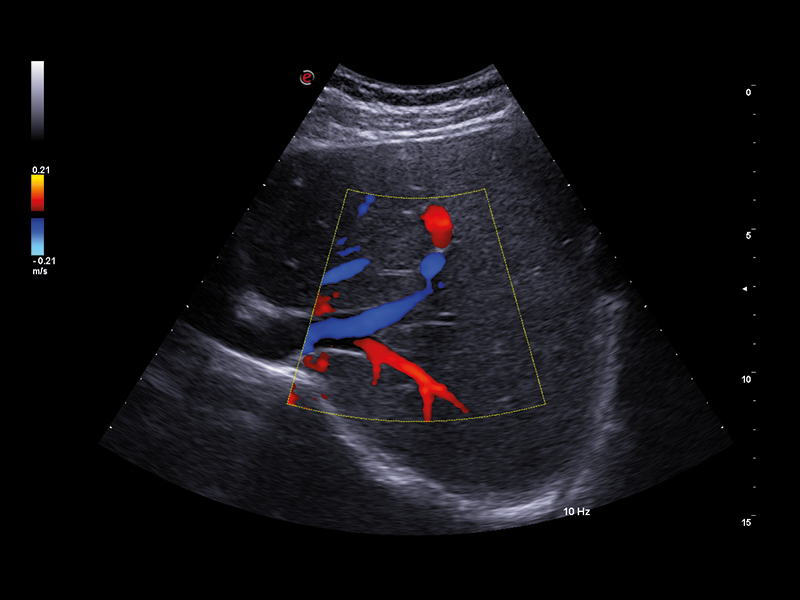

• microV: latest Esaote technology for microvascularisation visualisation with an elevated degree of sensitivity even in very small vessels and with slow flow detection. It enables advanced hemodynamic evaluation of lesions even in deep areas of the liver, thanks to exclusive filters that enhance only blood signals.

Lesions characterisation